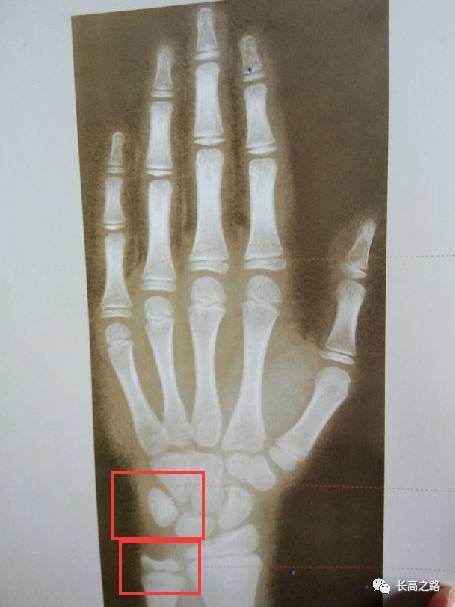

骨龄片怎么看

骨龄片怎么看,男孩骨龄图谱

13岁小振的骨龄片

儿童骨龄对照图表

教你简单识别孩子的骨龄片